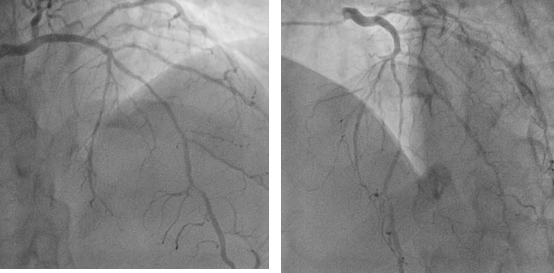

De nos jours, les stents cardiaques sont un bon choix pour les patients dont les artères coronaires sont obstruées à plus de 75 % et qui présentent de graves symptômes d'angine de poitrine, afin d'améliorer leurs symptômes et d'augmenter leur taux de survie. Il existe actuellement trois principaux types de stents cardiaques : les stents nus, les stents à élution médicamenteuse et les stents dégradables. Les stents nus et les stents à élution médicamenteuse couramment utilisés sont soutenus par des stents métalliques, et l'on craint que les personnes qui ont reçu un stent dans leur cœur ne soient exposées à un risque pour le stent cardiaque lorsqu'il pleut et qu'il y a des coups de tonnerre à l'extérieur. Est-ce vrai ?

Un stent cardiaque ressemble à une fine cage métallique qui est implantée et placée dans un vaisseau sanguin pour maintenir ouvert un vaisseau sanguin rétréci ou occlus. Il permet au vaisseau sanguin bloqué de circuler librement, augmentant ainsi l'apport sanguin au cœur et réduisant l'étendue de la nécrose myocardique. Un stent cardiaque est en fait très petit, mesurant 2 à 4 mm de diamètre et seulement quelques centimètres de long. Il s'agit d'un tube métallique creux, cylindrique et en forme de maille, généralement fabriqué en alliage de titane. En raison de sa petite taille et du fait qu'il est enveloppé dans l'endothélium des vaisseaux sanguins après l'implantation, il n'est pas affecté par le monde extérieur. Le tonnerre et la pluie ont encore moins d'effet sur lui.